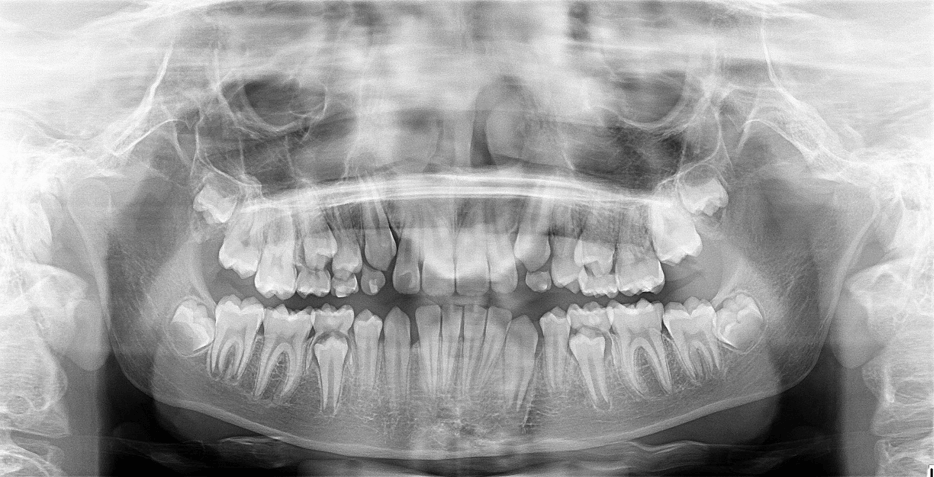

Al observar la radiografía panorámica (figura 2) se observa dentición mixta con secuencia adecuada de erupción y exfoliación, terceros molares en evolución intraosea.

Figura 2. Radiografía panorámica inicial